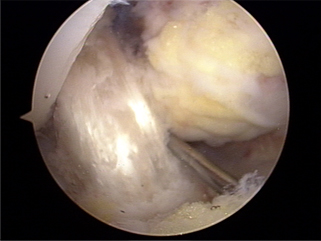

전방십자인대 파열

x-ray 사진